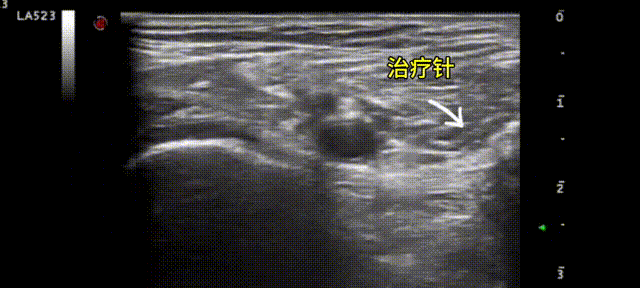

结合王先生的肌骨超声动态检查

超声介入团队制定出相应的治疗方案

在超声下进行全程可视化精准靶点治疗

该技术利用高频超声探头清晰显示肌肉、骨骼等组织的结构和微病变,在超声引导下精准定位、实时将药物注射至病灶位置进行微创治疗。

1. 实时动态监测:操作过程中全程可视化,避免损伤邻近重要结构,确保治疗的精准性。